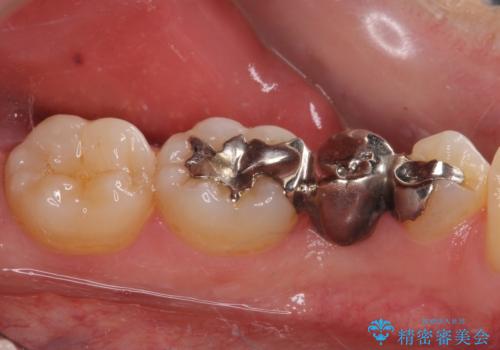

- 奥歯の銀歯が頻繁に外れるとのことで来院された患者様です。

欠損部分をインレーによるブリッジで治療してありましたが、外れやすく虫歯リスクが高いため、オールセラミックブリッジにて補綴することとしました。